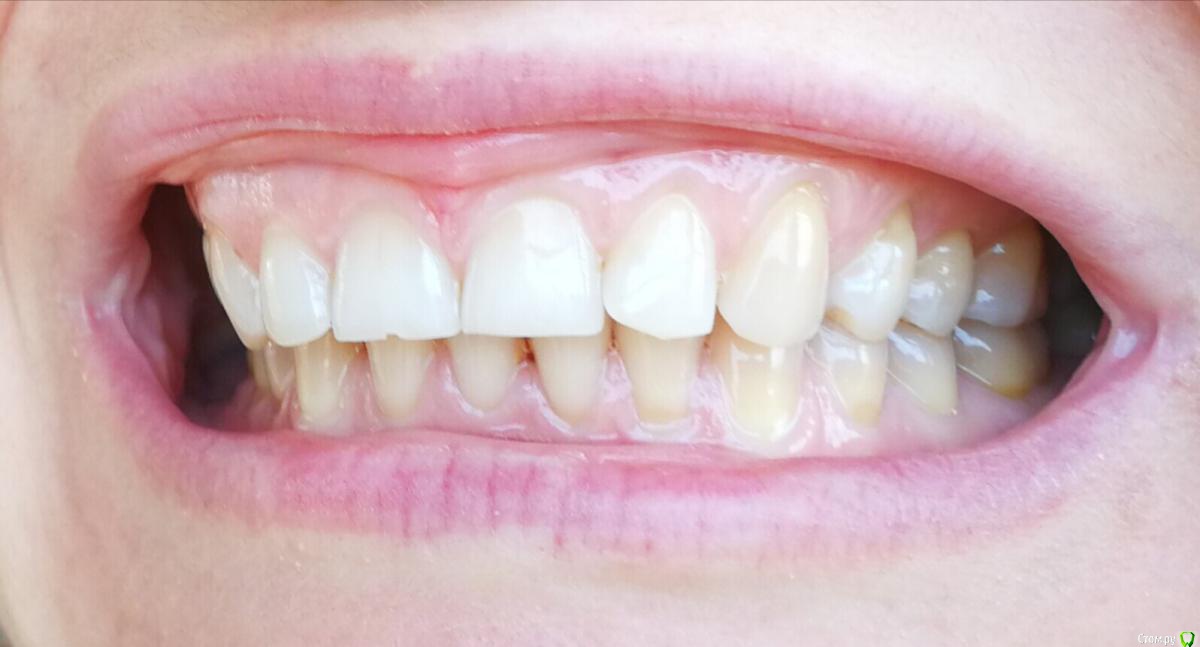

Ольга2000 Опубликовано 27 октября, 2019 Поделиться Опубликовано 27 октября, 2019 Здравствуйте. Мне 37 лет, ничего не беспокоит, нет повышенной чувствительности, кровоточивости. Мне кажется, что такие зубы у меня были последних лет 10, т.е. каких то изменений я не замечала.Делая последний раз гигиену ротовой полости врач сказала, что ей не нравится мой прикус. Через некоторое время я открывала зубами лекарство (понимаю, что так нельзя) и откололся кусочек переднего зуба. Это и подтолкнуло к записи к врачу.Первый врач осмотрел, сделал фотографии и сказал, что надо поднимать прикус с помощью пломб, пломбировать оголённые шейки зубов и ещё на отбеливание записал.Вчера была на приёме у ортодонта. Сделал снимок, сказал что с прикусом ничего не надо делать, посоветовал проконсультироваться с пародонтологом, т.к. поднимается кость. Я не знаю что мне делать. У меня следующие вопросы: 1. Надо ли поднимать прикус?2. Надо ли пломбировать оголение шеек зубов?3. На 11 и 21 зубах бороздки. Что с ними делать?4. Может капу на ночь сделать, чтобы зубы не стирались?5.И вообще что мне надо делать в обязательном порядке? И в необязательном тоже. Спасибо за ответы. Ссылка на комментарий

krokomot Опубликовано 27 октября, 2019 Поделиться Опубликовано 27 октября, 2019 По вашим фотографиям не возможно сказать нужно ли вам поднимать прикус, скорее всего да, слевой стороны у вас стираемость зубов, зубы попадают бугор на бугор, есть смещение центральной линии. также с левой стороны 6й зуб визуально не в очень хорошем состоянии. нужно ли вам что то делать? вы должны решить сами, зубы слева на буграх сточены до дентина, то есть эмаль уже полностью стерта далее с течением времени зубы начнут изнашиваться всё быстрее и быстрее. наличие полосок на нижних зубах можно не пломбировать, а скорректировать чистку зубов перейдя на выметающие движения , а не горизонтальные. если вы хотите еще 37 лет прожит со своими собственными зубами и не испытывать проблем, то нужно пройти ортодонтическое лечение и восстановить анатомию стертых зубов керамикой. Это остановит стираемость, а можете это сделать через 10 лет, но объем вмешательства возрастет кратно... 1 Ссылка на комментарий